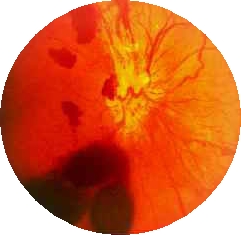

비문증

당뇨망막병증(Diabetic retinopathy)

관련질환

망막 박리

인슐린 의존성 당뇨병

인슐린 비의존성 당뇨병

유리체 출혈

당뇨망막병증

망막 박리(Retinal detachments & breaks)

망막 출혈

망막 전막

고혈압

포도막염

마르판 증후군

망막 정맥 폐쇄

당뇨병

망막 열공

맥락막 흑색종(Choroidal melanoma)

유리체 출혈(Vitreous hemorrhage)